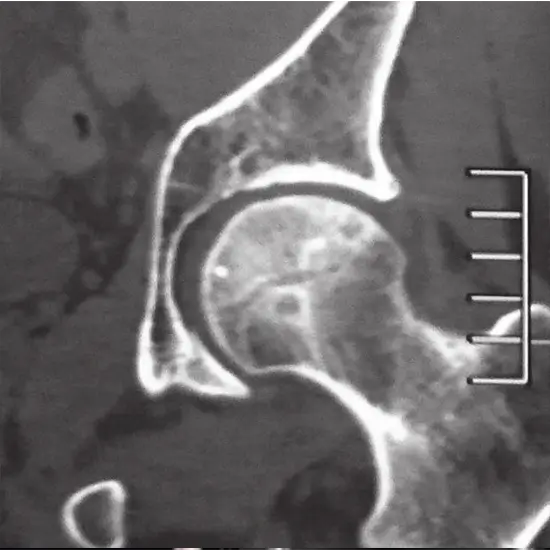

CT Scan Hip Joint Test

A hip CT scan can help diagnose a variety of hip conditions, including fractures, femoroacetabular impingement, bone tumours, calcified intra-articular bodies, arthritis, and arthritis.